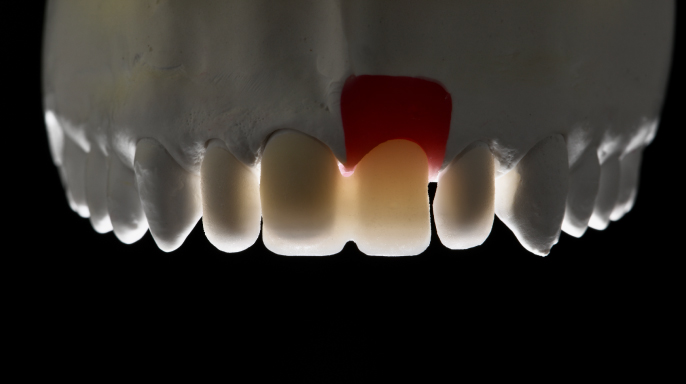

Klinický přístup k plně keramickým hybridním rehabilitacím zajišťujícím dlouhodobou stabilitu a vysoce estetické výsledky bez použití kovových komponent.

Moderní stomatologie prochází technologickou revolucí, kterou pohání integrace pokročilých digitálních nástrojů v diagnostice, plánování a léčbě. Mezi nimi se počítačem řízená implantologie stala základním pilířem, zejména u složitých výkonů, jako jsou estetické rekonstrukce a celková rehabilitace čelistního oblouku.

Digitální pracovní postupy ve stomatologii přinesly revoluci v přístupu odborníků ke složitým zákrokům – zlepšují přesnost, efektivitu a dosažené klinické výsledky. Mezi digitálními inovacemi se výrazně prosazují systémy pro plnou navigaci...